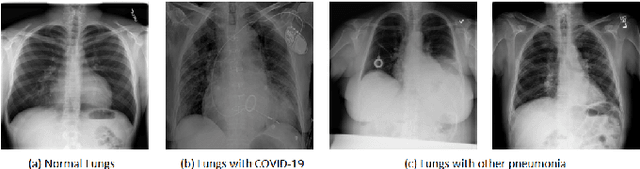

It is evident that the infection with this severe acute respiratory syndrome coronavirus 2 (SARS-CoV-2) starts with the upper respiratory tract and as the virus grows, the infection can progress to lungs and develop pneumonia. According to the statistics, approximately 14\% of the infected people with COVID-19 have severe cough and shortness of breath due to pneumonia, because as the viral infection increases, it damages the alveoli (small air sacs) and surrounding tissues. The conventional way of COVID-19 diagnosis is reverse transcription polymerase chain reaction (RT-PCR), which is less sensitive during early stages specially, if the patient is asymptomatic that may further lead to more severe pneumonia. To overcome this problem an early diagnosis method is proposed in this paper via one-class classification approach using a novel pinball loss function based one-class support vector machine (PB-OCSVM) considering posteroanterior chest X-ray images. Recently, several automated COVID-19 diagnosis models have been proposed based on various deep learning architectures to identify pulmonary infections using publicly available chest X-ray (CXR) where the presence of less number of COVID-19 positive samples compared to other classes (normal, pneumonia and Tuberculosis) raises the challenge for unbiased learning in deep learning models that has been solved using class balancing techniques which however should be avoided in any medical diagnosis process. Inspired by this phenomenon, this article proposes a novel PB-OCSVM model to work in presence of limited COVID-19 positive CXR samples with objectives to maximize the learning efficiency while minimize the false-positive and false-negative predictions. The proposed model outperformed over recently published deep learning approaches where accuracy, precision, specificity and sensitivity are used as performance measure parameters.